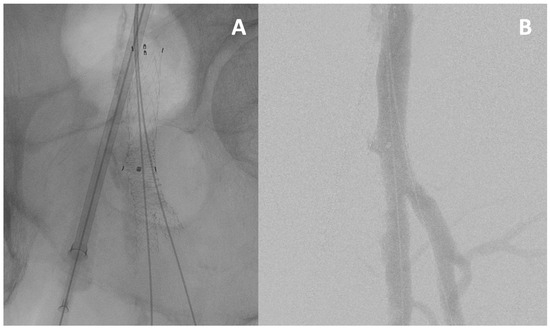

3.6. Lesion Crossing

3.6.1. True Lumen Crossing Techniques

3.6.2. Sub-Intimal Crossing Techniques

3.6.3. Retrograde Superficial or Deep Femoral Artery Puncture